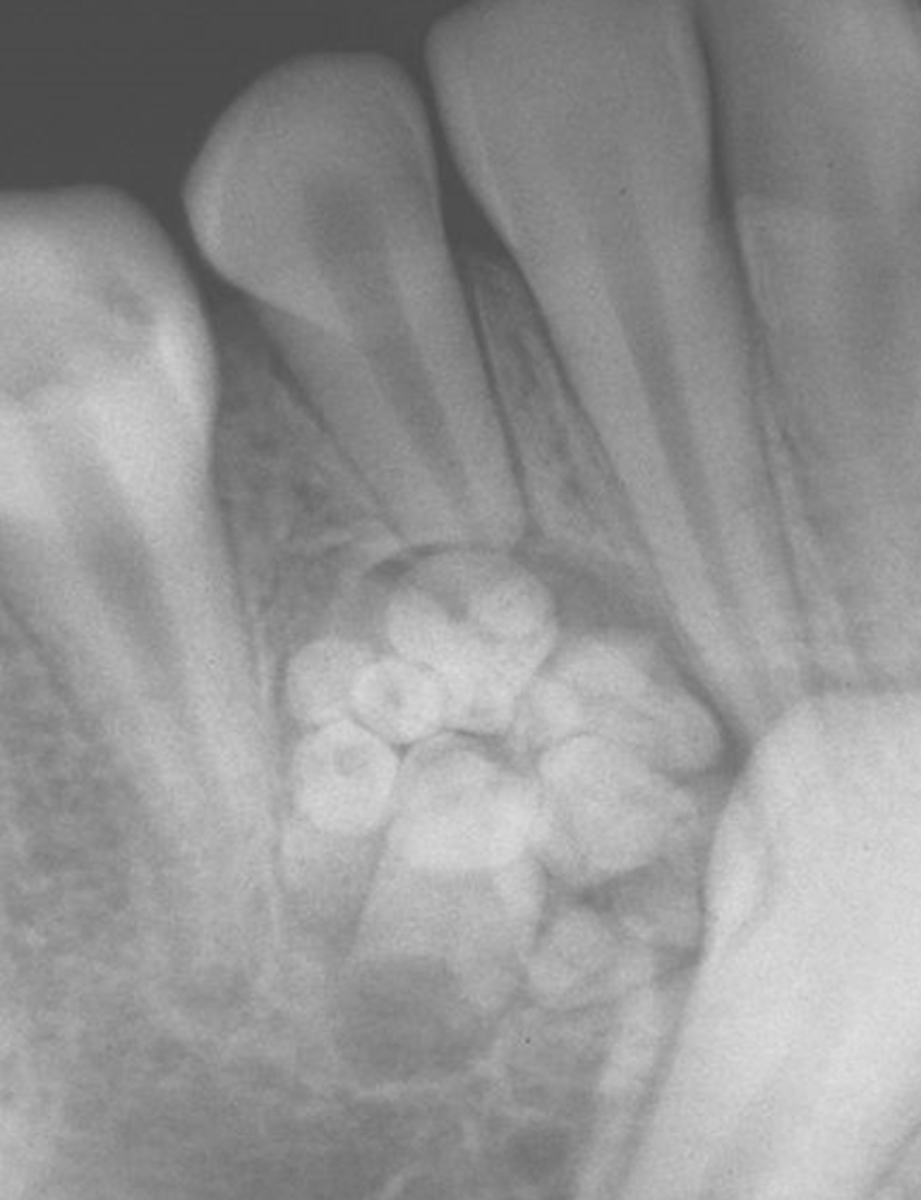

What are radiographic features of complex odontomas?

radiopaque mass

What is the treatment and prognosis for complex odontomas?

⢠treatment: surgical excision

⢠prognosis: excellent

What is the population of complex odontomas?

young: 10-20 years old